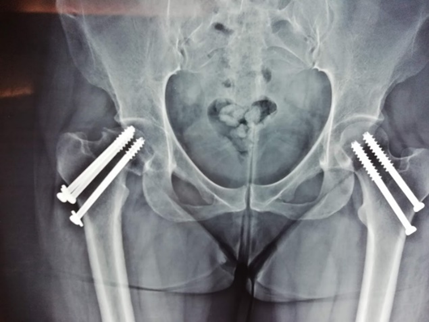

Γυναίκα 45 ετών με αμφοτερόπλευρη αναπτυξιακή δυσπλασία (ΣΕΙ)